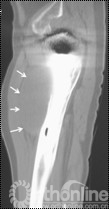

所有炎性假瘤均行瘤样包块切除或清除。患者侧卧位,炎性假瘤位于髂窝者6例,取髂腹股沟入路,显露髂窝骨盆内侧壁髋臼内侧处。6例骨盆内侧壁处存在炎性假瘤,假瘤包块边界清晰,与周围组织无粘连,3例囊内为淡黄色砂粒、干酪样组织(图3),1例包块内为褐色沙粒样物,2例为淡黄色、半透明微混浊水样液。包块均通过髂骨内板骨缺损区与髋臼骨溶解病灶相通。仔细分离囊壁与周围组织并将囊壁完全切除。1例右股骨侧炎性假瘤患者,侧卧位患侧在上,沿原切口入路,切开深筋膜后,于股四头肌深部可触及质软包块,分离股四头肌,显露包块,包膜与股四头肌无粘连,切开包膜,见褐色沙粒样物(图4)。彻底清除褐色物,见股骨外侧部分皮质骨溶解破坏。取同种异体皮质骨板植于股骨外侧骨缺损处,多道双股钢丝环扎固定,周围植入同种异体松质骨颗粒。所用同种异体骨均来自四川省骨库,经深低温冷冻处理。

图4  股骨侧炎性假瘤,包膜与股四头肌无粘连,切开包膜,见褐色沙粒样物